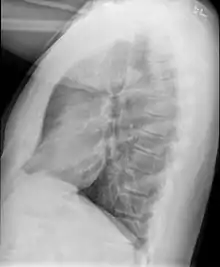

Example of early disease with mild flattening of the diaphragm

Bronchiolitis obliterans is often diagnosed based on the symptoms of obstructive lung disease following lung injury. The definitive diagnosis is through biopsy, but due to the variable distribution of lesions, leading to falsely negative tests, and invasive nature of this procedure it is often not performed.[6][11] Several tests are often needed to diagnose bronchiolitis obliterans, including spirometry, diffusing capacity of the lung tests (DLCO), lung volume tests, chest X-rays, high-resolution CT (HRCT), and lung biopsy.[11][4]

Medical imaging

Early in the disease chest radiography is typically normal but may show hyperinflation.[6] As the disease progresses a reticular pattern with thickening of airway walls may be present.[4][6] HRCT can also show air trapping when the person being scanned breathes out completely; it can also show thickening in the airway and haziness in the lungs.[11] A common finding on HRCT is patchy areas of decreased lung density, signifying reduced vascular caliber and air trapping. This pattern is often described as a "mosaic pattern", and may indicate bronchiolitis obliterans.[6]